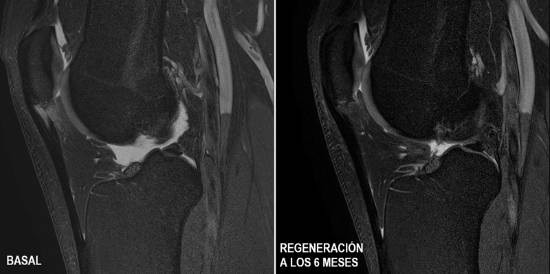

To demonstrate this, a double-blind clinical trial was conducted, comparing two groups of patients, one treated with PRP (Platelet-Rich Plasma) and the other with CMSC. The group treated with PRP showed no improvement, while those treated with CMSC achieved an unprecedented degree of tendon structure regeneration in 100% of patients, with a return to sporting activity after 2 months.

Over the past 20 years, ITRT has provided scientific evidence and demonstrated in clinical trials that new tissue can be created in any tendon and the injury can be repaired as if it had never happened. During this time, the centre has treated almost 150 patients for injuries to all tendons, including the patellar, Achilles, hamstring and supraspinatus tendons, among them international elite athletes.